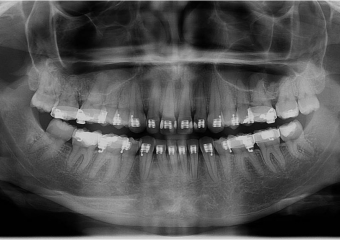

Raio x inicial